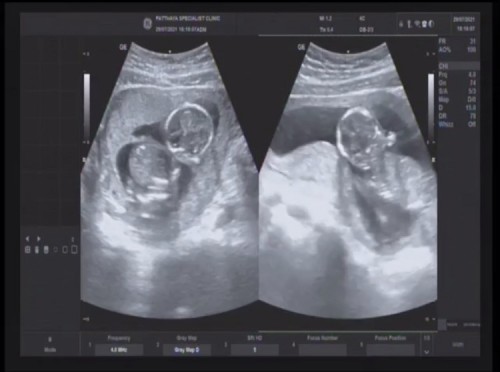

เราไปหาหมอเพราะเราท้องได้4เดือนแต่ท้องแข็งบ่อยเลยไปหาหมอ บอกมาอัลตซาวด์คะ เข้าห้องอัลซาวด์ หมอมานั่งข้างเตียงเพื่อซาวด์ ทาเจลลงบนท้องเอาที่ซาวด์จิ้ม 10 วินาที คำว่าพูดหมอคือ “อ้าวท้องแฝดนิ” น้ำตาไหลเลยจ้า เพราะทั้งญาติแฟนและครอบครัวเราไม่มีใครมีแฝด แต่ยังไม่รู้เพศ มีภาพมาให้ชมกันคะ โดนหมอทักอีกว่า ตัวใหญ่ทั้งคู่เลย👼🏻❤️👼🏻